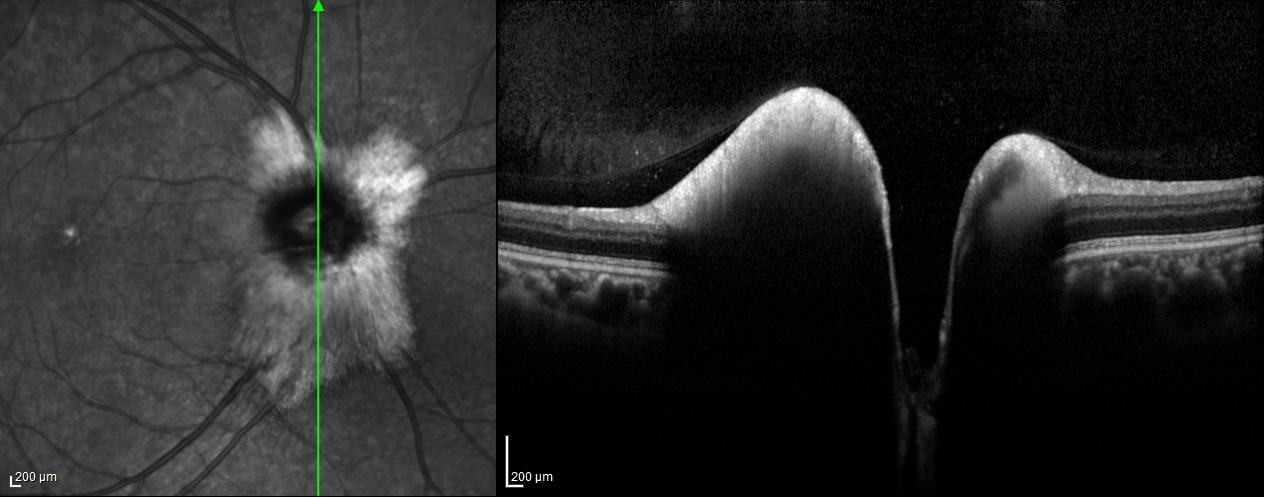

Optical coherence tomography scans through these lesions demonstrated a thickened and hyperreflective retinal nerve fiber layer.

Myelinated retinal nerve fibers are a rare, benign finding in the eye. Normally, retinal nerve fibers are unmyelinated, but in MRNF, myelin extends into the retina, appearing as white or gray striated patches near the optic disc. They are usually discovered incidentally during routine eye exams and are typically asymptomatic. While vision is often normal, MRNF can sometimes be associated with high myopia or amblyopia. Optical coherence tomography (OCT) shows a thickened, hyperreflective retinal nerve fiber layer corresponding to the lesion. No treatment is needed, but regular monitoring is recommended to rule out other retinal pathologies.